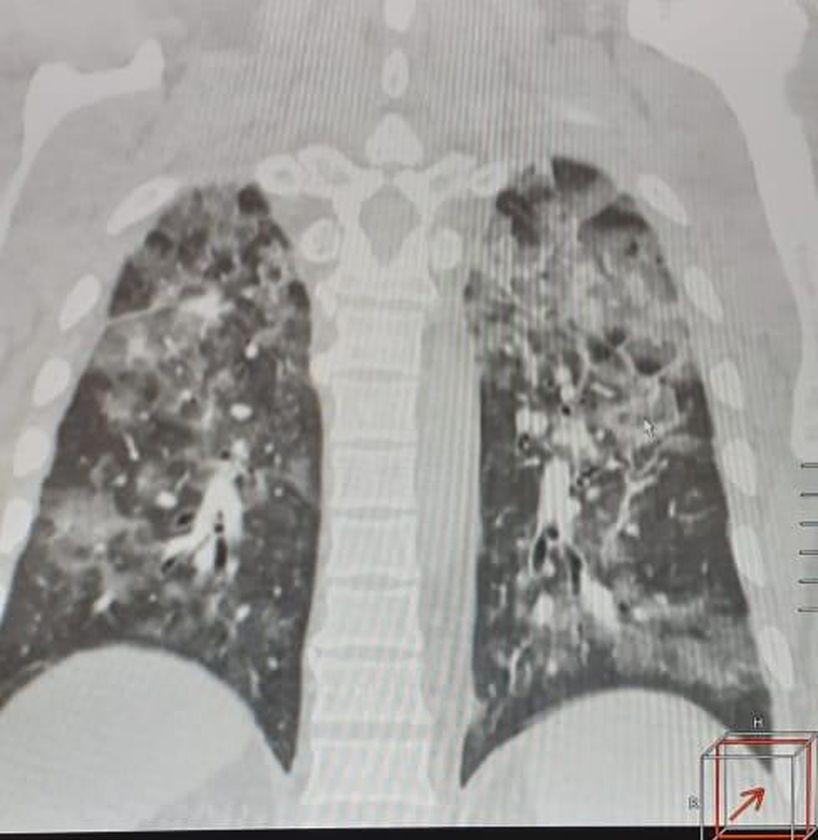

Coronavirus

Pneumonia

Covid 19

Pandemic

Lungdamage